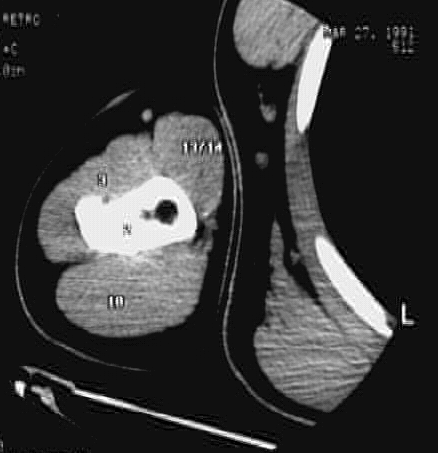

Upper Limbs:Upper Limb Zoom 1 of 2: